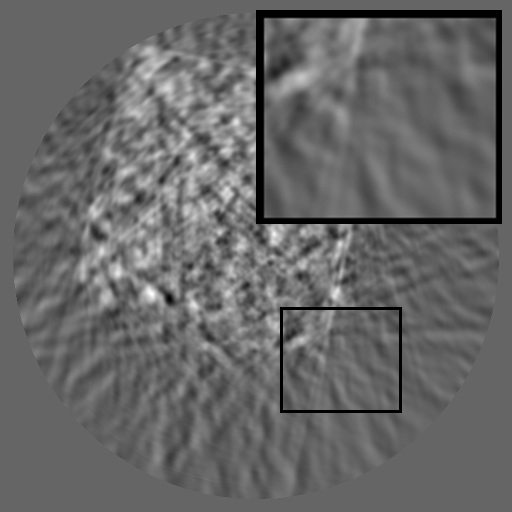

Figure 2: Qualitative inpainting results on TomoBank (lines 1 to 2) and LoDoPaB (lines 3 to 4) with random mask (ratio = 0.8) at 1024×\times1024 resolution. Odd columns and even columns show the sinograms and reconstructed images, respectively.

Inpainting Quality. Tab 2 summarizes accuracy results. At 2048×\times2048 resolution, HiSin achieves the best performance among all baselines while remaining memory-efficient, demonstrating its ability to extend high-quality inpainting to resolutions where other diffusion models fail. At 1024×\times1024, HiSin delivers accuracy comparable to its computation-intensive counterpart RePaint, showing that our optimizations do not compromise fidelity at moderate scales. Compared to DiffIR and HiDiffusion, HiSin consistently achieves higher SSIM and PSNR across mask ratios, with improvements up to +0.03 SSIM and +1.8 dB PSNR. Fig 2 visualizes sinogram inpainting and reconstructed images, where HiSin produces nearly indistinguishable results from RePaint. These findings confirm that HiSin fundamentally extends diffusion-based inpainting to 2048×\times2048 resolution in a more memory- and runtime-efficient manner.